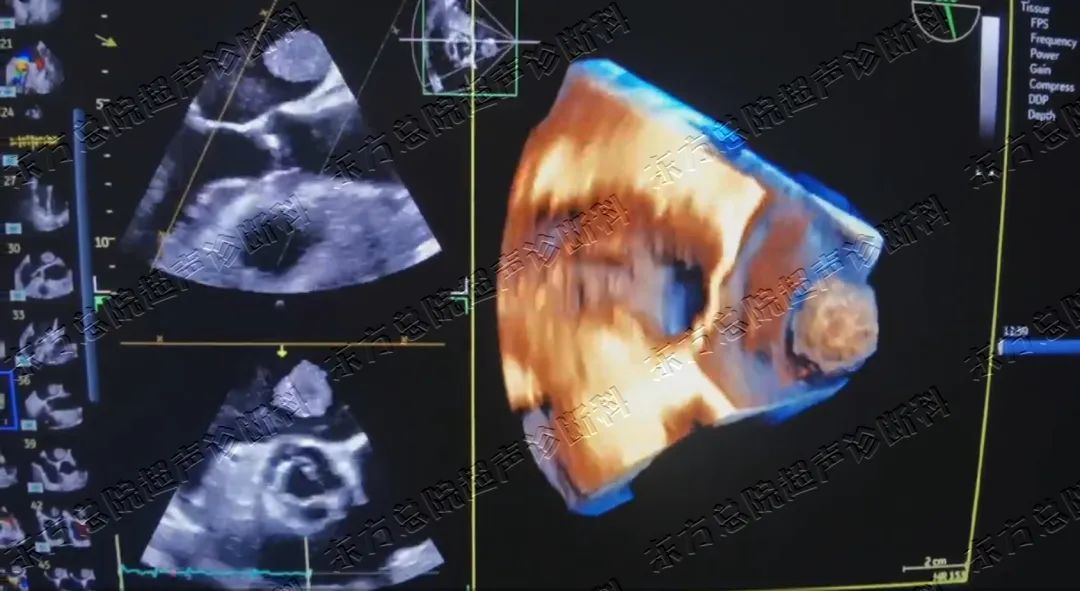

▲左房内占位经食道心脏四维成像